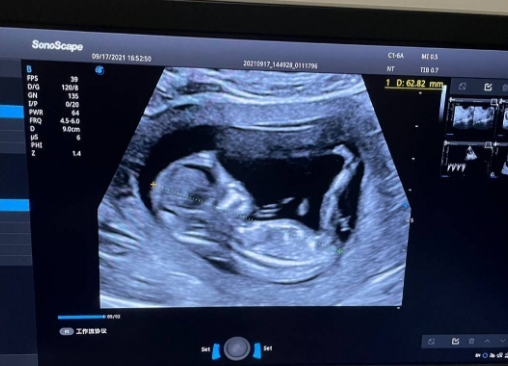

想要准确了解胎儿大小,医学上的核心依据是B超检查,而非宫高。B超可以通过测量胎儿的双顶径、头围、腹围、股骨长等多项指标,结合孕周计算出胎儿的预估体重,这些数据能更精准地反映胎儿的实际发育情况。

比如通过腹围可以判断胎儿腹部脂肪堆积情况,股骨长能反映胎儿骨骼发育状态,综合这些指标得出的评估结果,比单一的宫高数值可靠得多。临床中,医生会将宫高测量结果与B超数据相互印证,若两者出现明显偏差,再进一步排查原因,这样才能确保判断的准确性。